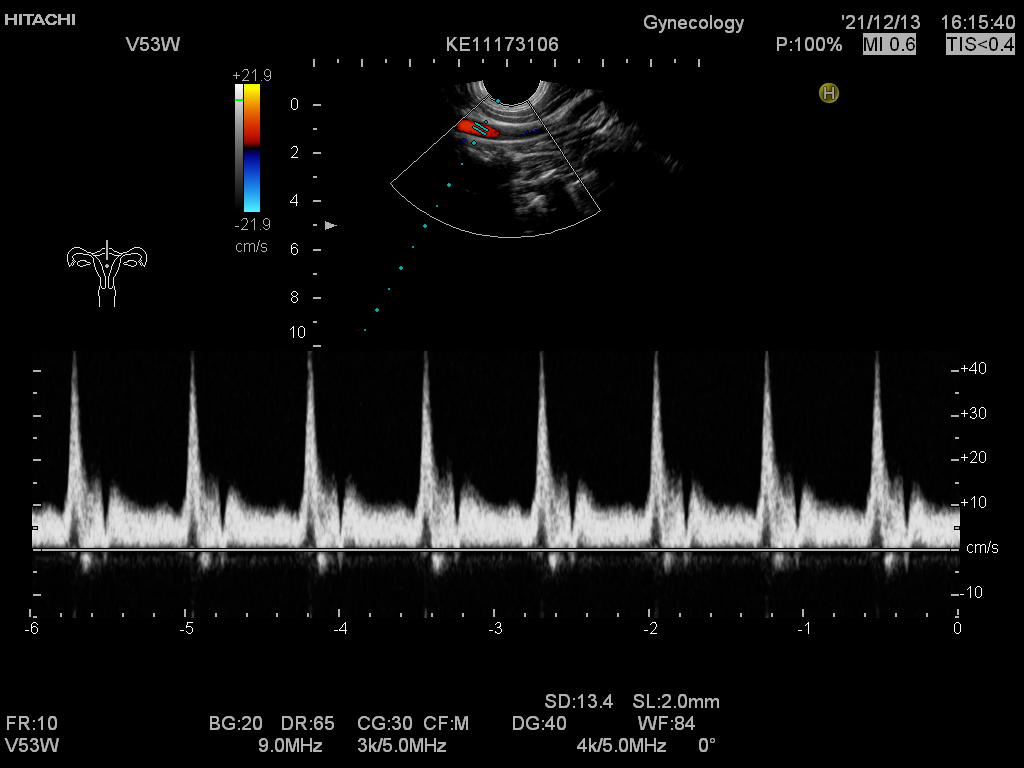

Hitachi EUP-V53W Ref Endocavity Vaginal – HI VISION

Hitachi Endocavity EUP-V53W Transvaginal

Hitachi EUP-V53W Endocavity Vaginal – HI VISION

Frequency Range: 8 – 4 MHz

Scan Width Convex: 10 mm Radius

Scan Angle Convex: 200° FOV

HI VISION Connector

Hitachi EUP-V53W Endocavity Vaginal – HI VISION for Endovaginal

Compatible with Hitachi Hi Vision systems